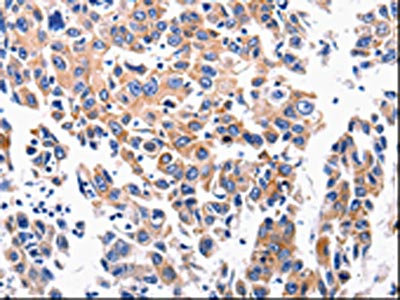

The image is immunohistochemistry of paraffin-embedded Human lung cancer tissue using CSB-PA025395(ACE2 Antibody) at dilution 1/200. (Original magnification: ×200)